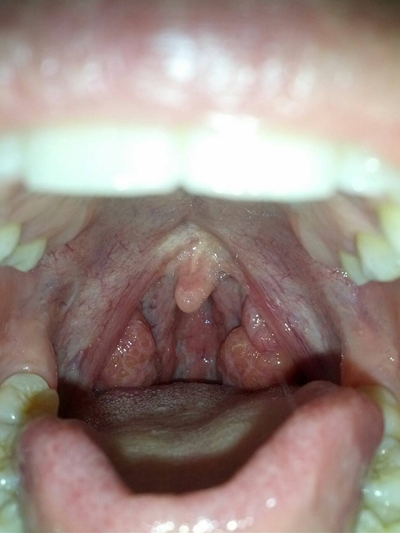

食道炎的症狀圖

食道炎的症狀圖 (9)

食道炎的症狀圖 (7)

食道炎的症狀圖 (8)

食道炎的症狀圖 (58)